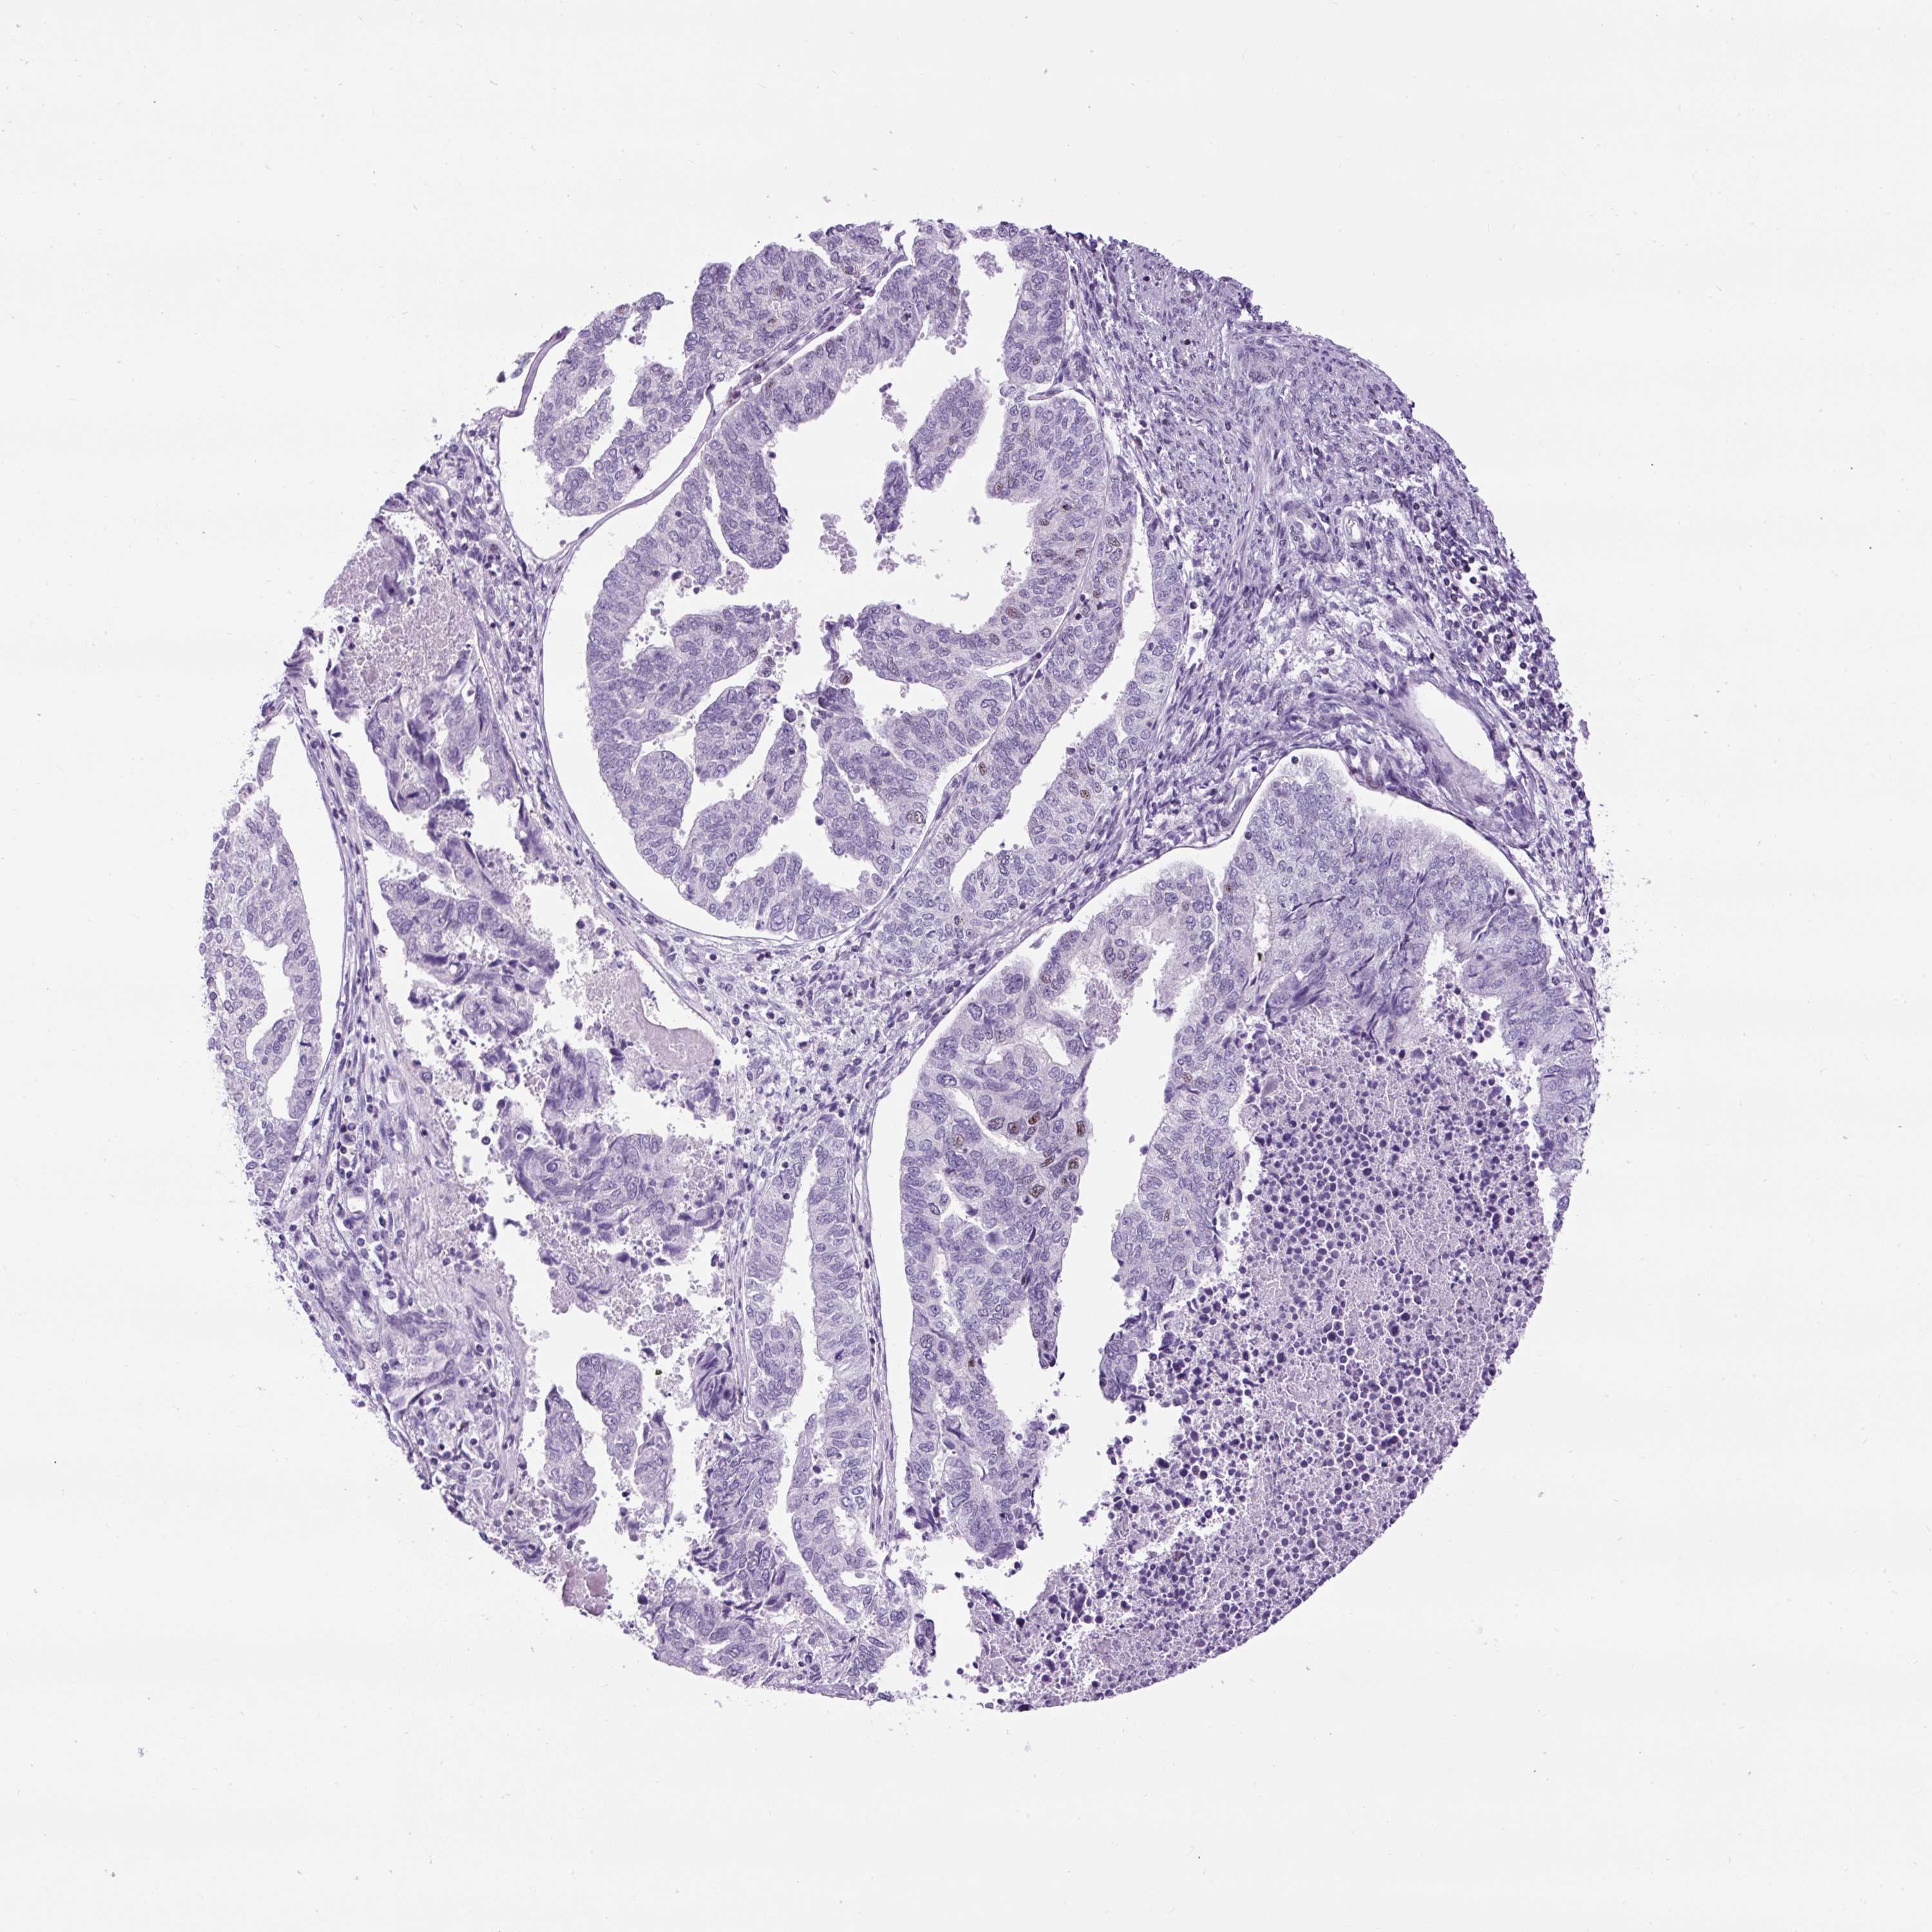

ENDOMETRIAL CANCER - Protein expressioni

A mouse-over function shows sample information and annotation data. Click on an image to view it in a full screen mode. Samples can be filtered based on level of antibody staining by selecting one or several of the following categories: high, medium, low and not detected. The assay and annotation is described here.

Note that samples used for immunohistochemistry by the Human Protein Atlas do not correspond to samples in the TCGA dataset.

Antibody stainingi

Antibody staining in the annotated cell types in the current human tissue is reported as not detected, low, medium, or high, based on conventional immunohistochemistry profiling in selected tissues. This score is based on the combination of the staining intensity and fraction of stained cells.

Each image is clickable and will lead to virtual microscopy that enables deeper exploration of all samples and also displays staining intensity scores, fraction scores and subcellular localization as well as patient and tissue information for each sample.

Antibody HPA054900

Staining

High

Medium

Low

Not detected

Intensity

Strong

Moderate

Weak

Negative

Quantity

>75%

75%-25%

<25%

None

Location

Nuclear

Cytoplasmic/membranous

Cytoplasmic/membranous,nuclear

Adenocarcinoma, NOS